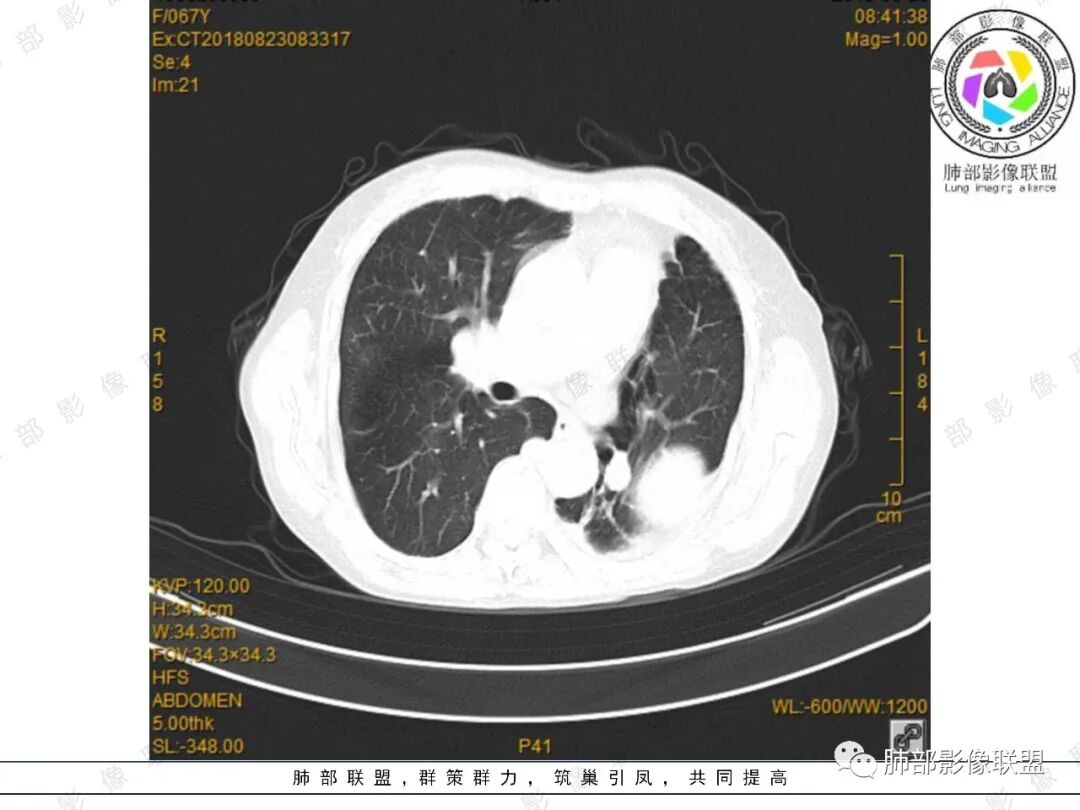

采莲:中年女性,有便血病史,左肺上叶椭圆形肿块,边缘光滑,长轴与胸膜平行,与胸膜宽基底相连,内部密度较均匀,有低密度区,密度较高,强化不明显,脊柱旁胸膜增厚,有便血病史,不知道是不是慢性,考虑来源胸膜,髓外造血?脾脏不会看。其他神经源性肿瘤?

小强:脾大,延迟强化均匀,无明显占位,左胸膜下孤性增厚,局限性膨大,强化不均匀,先考虑EMH,不太支持的是临近骨质没有膨大。

看图说话:左肺肿块,边缘光滑,密度不均匀,不均匀强化,胸腔少量积液,纵隔肿大淋巴结。脾脏增大,见肿块影,不均匀强化,一元论,考虑淋巴瘤,转移瘤。

水晶石头:患者老年年女性,便血两天就诊,查NSE稍升高。胸部CT:左肺上叶类圆形肿块,边缘光滑,边界清楚,长轴与胸膜平行,与胸膜宽基底相连,内部密度较均匀,有低密度区,强化轻中度强化。综合考虑来源胸膜来源,胸膜孤立性纤维瘤可能大。鉴别其神经源性肿瘤。

月亮圆了!:左肺上叶胸膜下肿块,宽基底与胸膜相连,边缘清晰,局部肺组织受压,支气管显示不佳,平扫密度不均匀,增强后,可见轻度不均匀强化,纵隔光滑,无分叶,无毛刺,周围组织无牵拉,收缩,内部有不均匀低密度,脾脏明显肿大,脾内多发类圆形低密度影,增强后,轻度强化,有便血,考虑可能:1:淋巴瘤2:脾梗死。